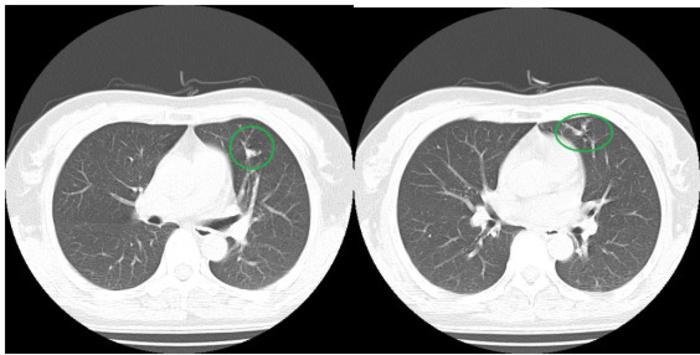

辅助检查:血常规:白细胞20.05×109/L;中性粒细胞77.3%;红细胞、血小板正常。胸部CT如下:

胸部CT未见明显异常,于是我们给他做了支气管镜检查,在患者左肺上叶支气管发现了支气管异物——鱼刺。

图6-7

支气管镜下发现异常后,我们再仔细回看做支气管镜检查前的胸部CT:

图8

可能有经验且细心的同道发现了该病灶,但如果这张图是放在没有任何提示的361张图片里,你确定还能发现病灶吗?当时影像科和临床医师都没有发现,如果我不做标识,相信非常多的人也看不出来。

图9

这个病例真实的警示我们,不明原因的胸闷、气短、呼吸困难,包括长期咳嗽,特别是胸部CT显示长期在固定部位出现肺不张或反复感染者,支气管镜检查更是不可或缺,不仅具有突出优势,甚至是明确诊断不可替代的唯一手段。